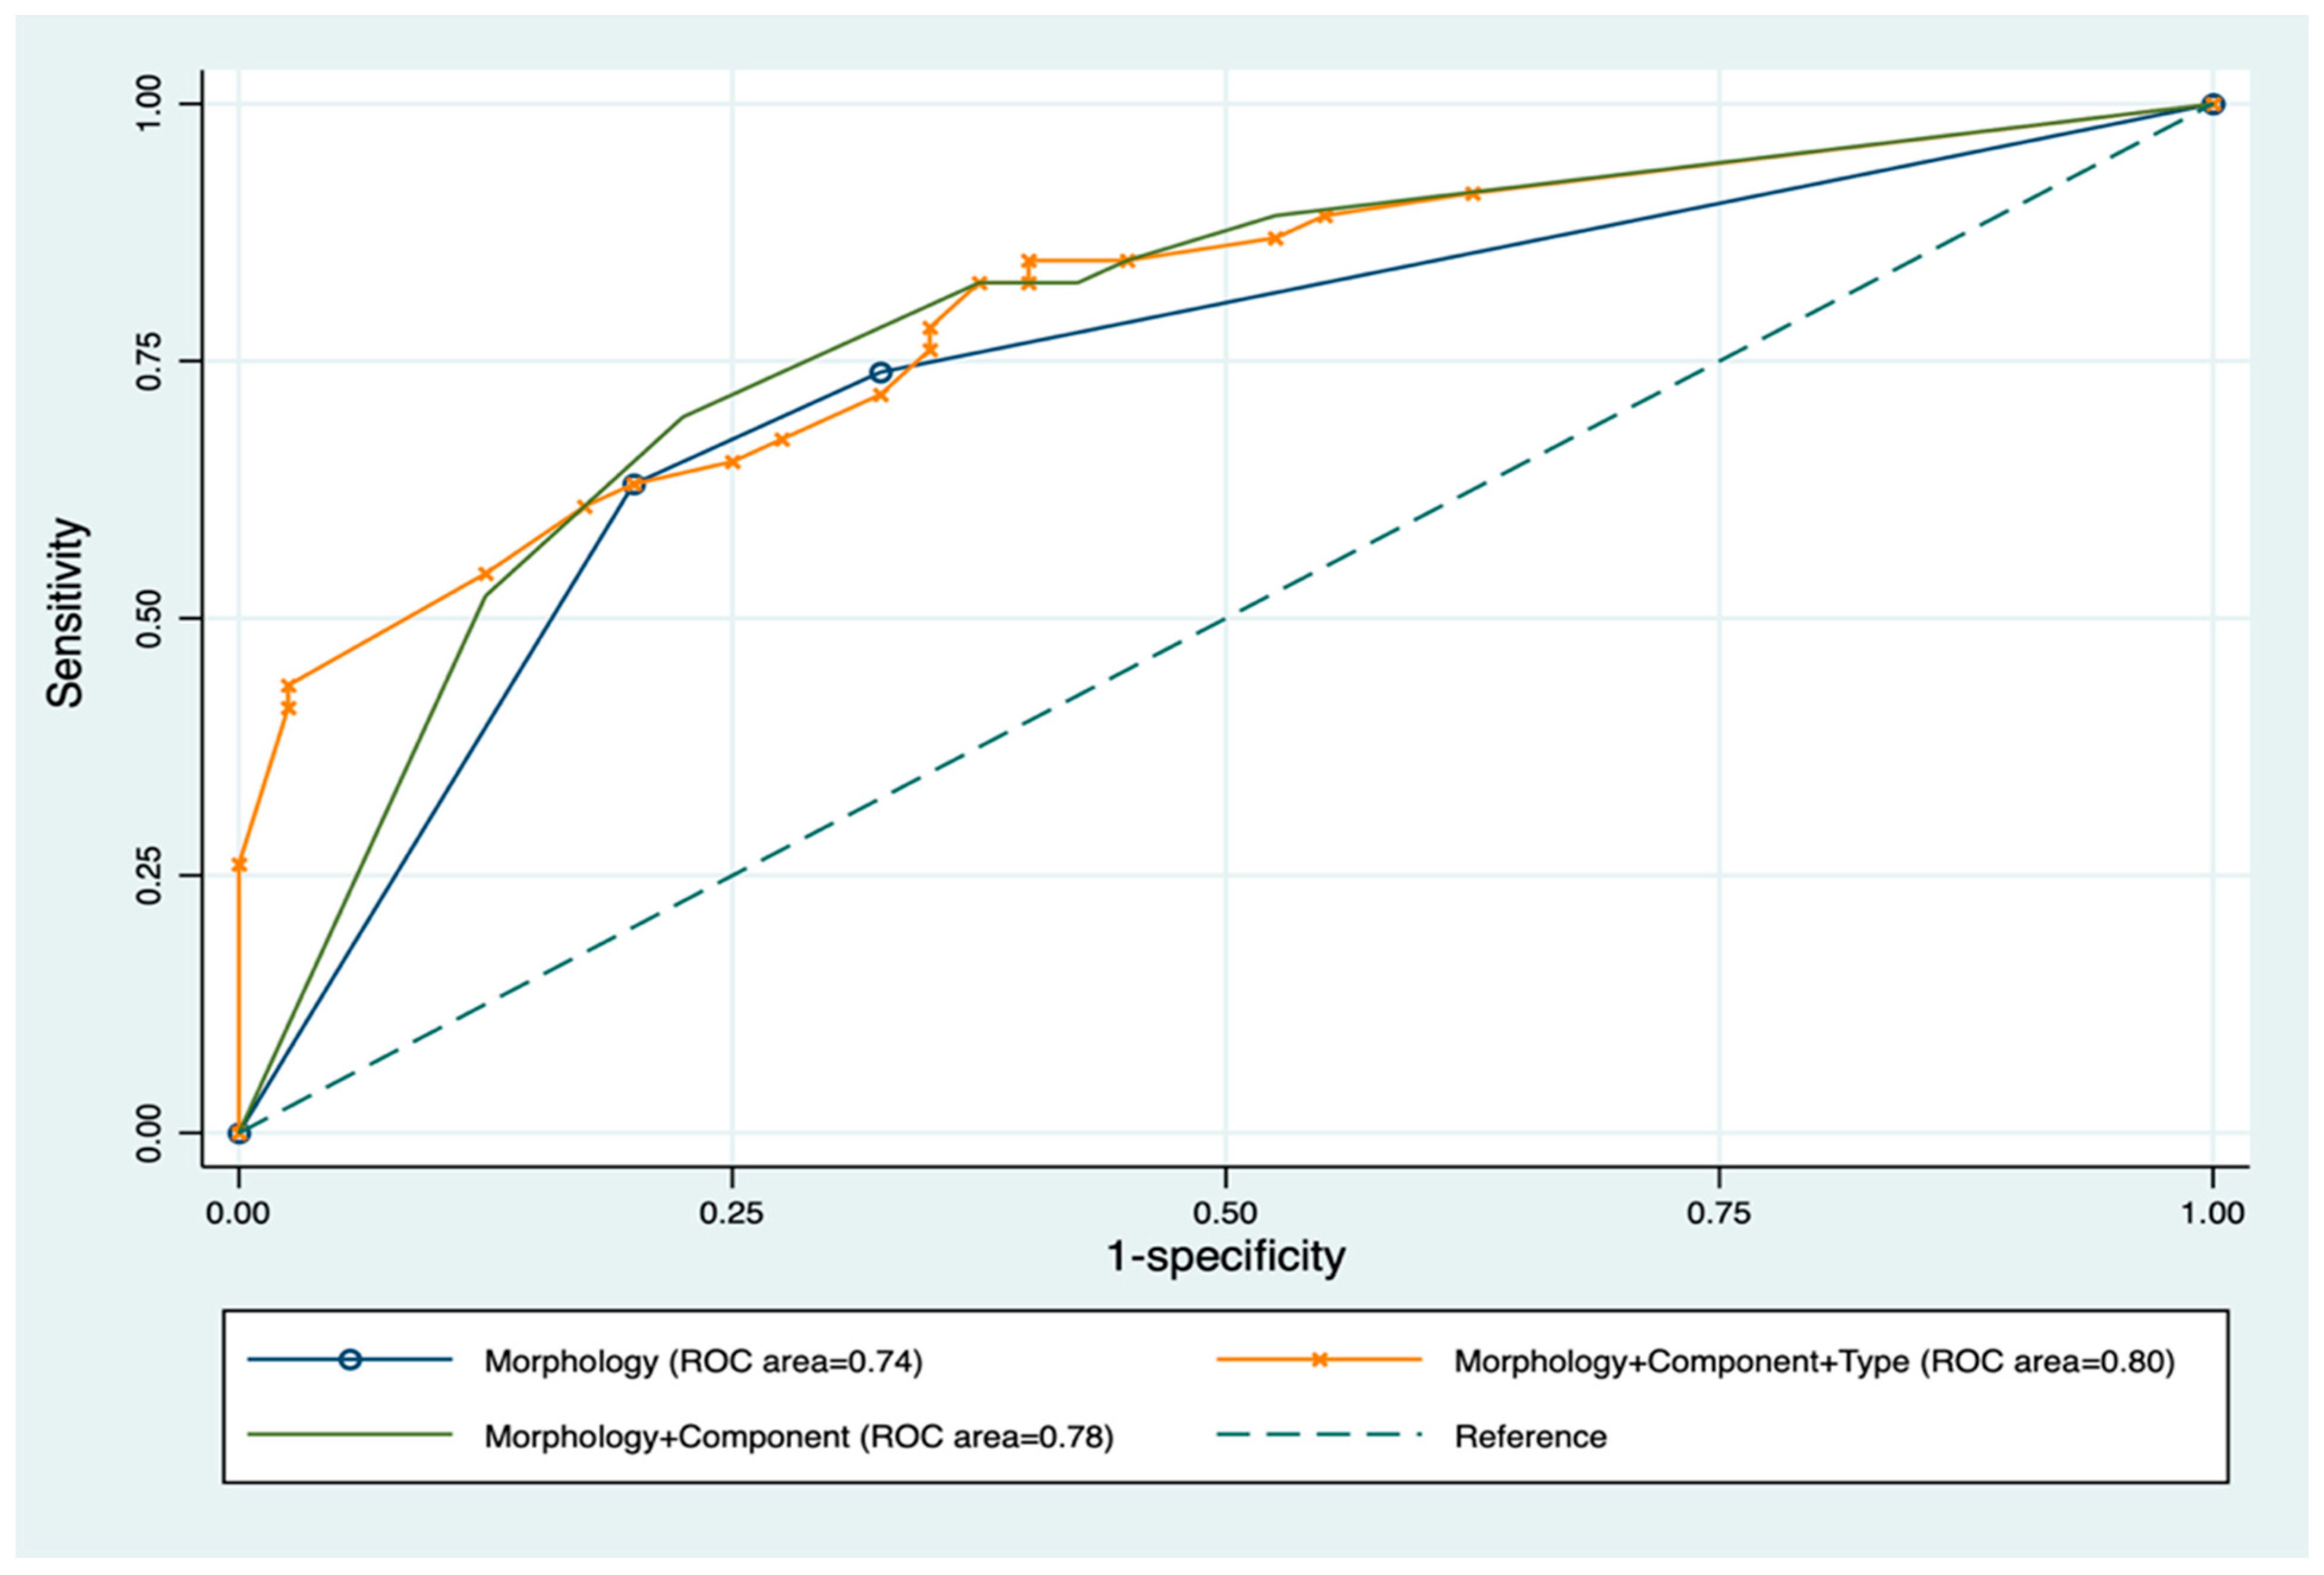

2.6. Statistical Analysis

3. Results

4. Discussion